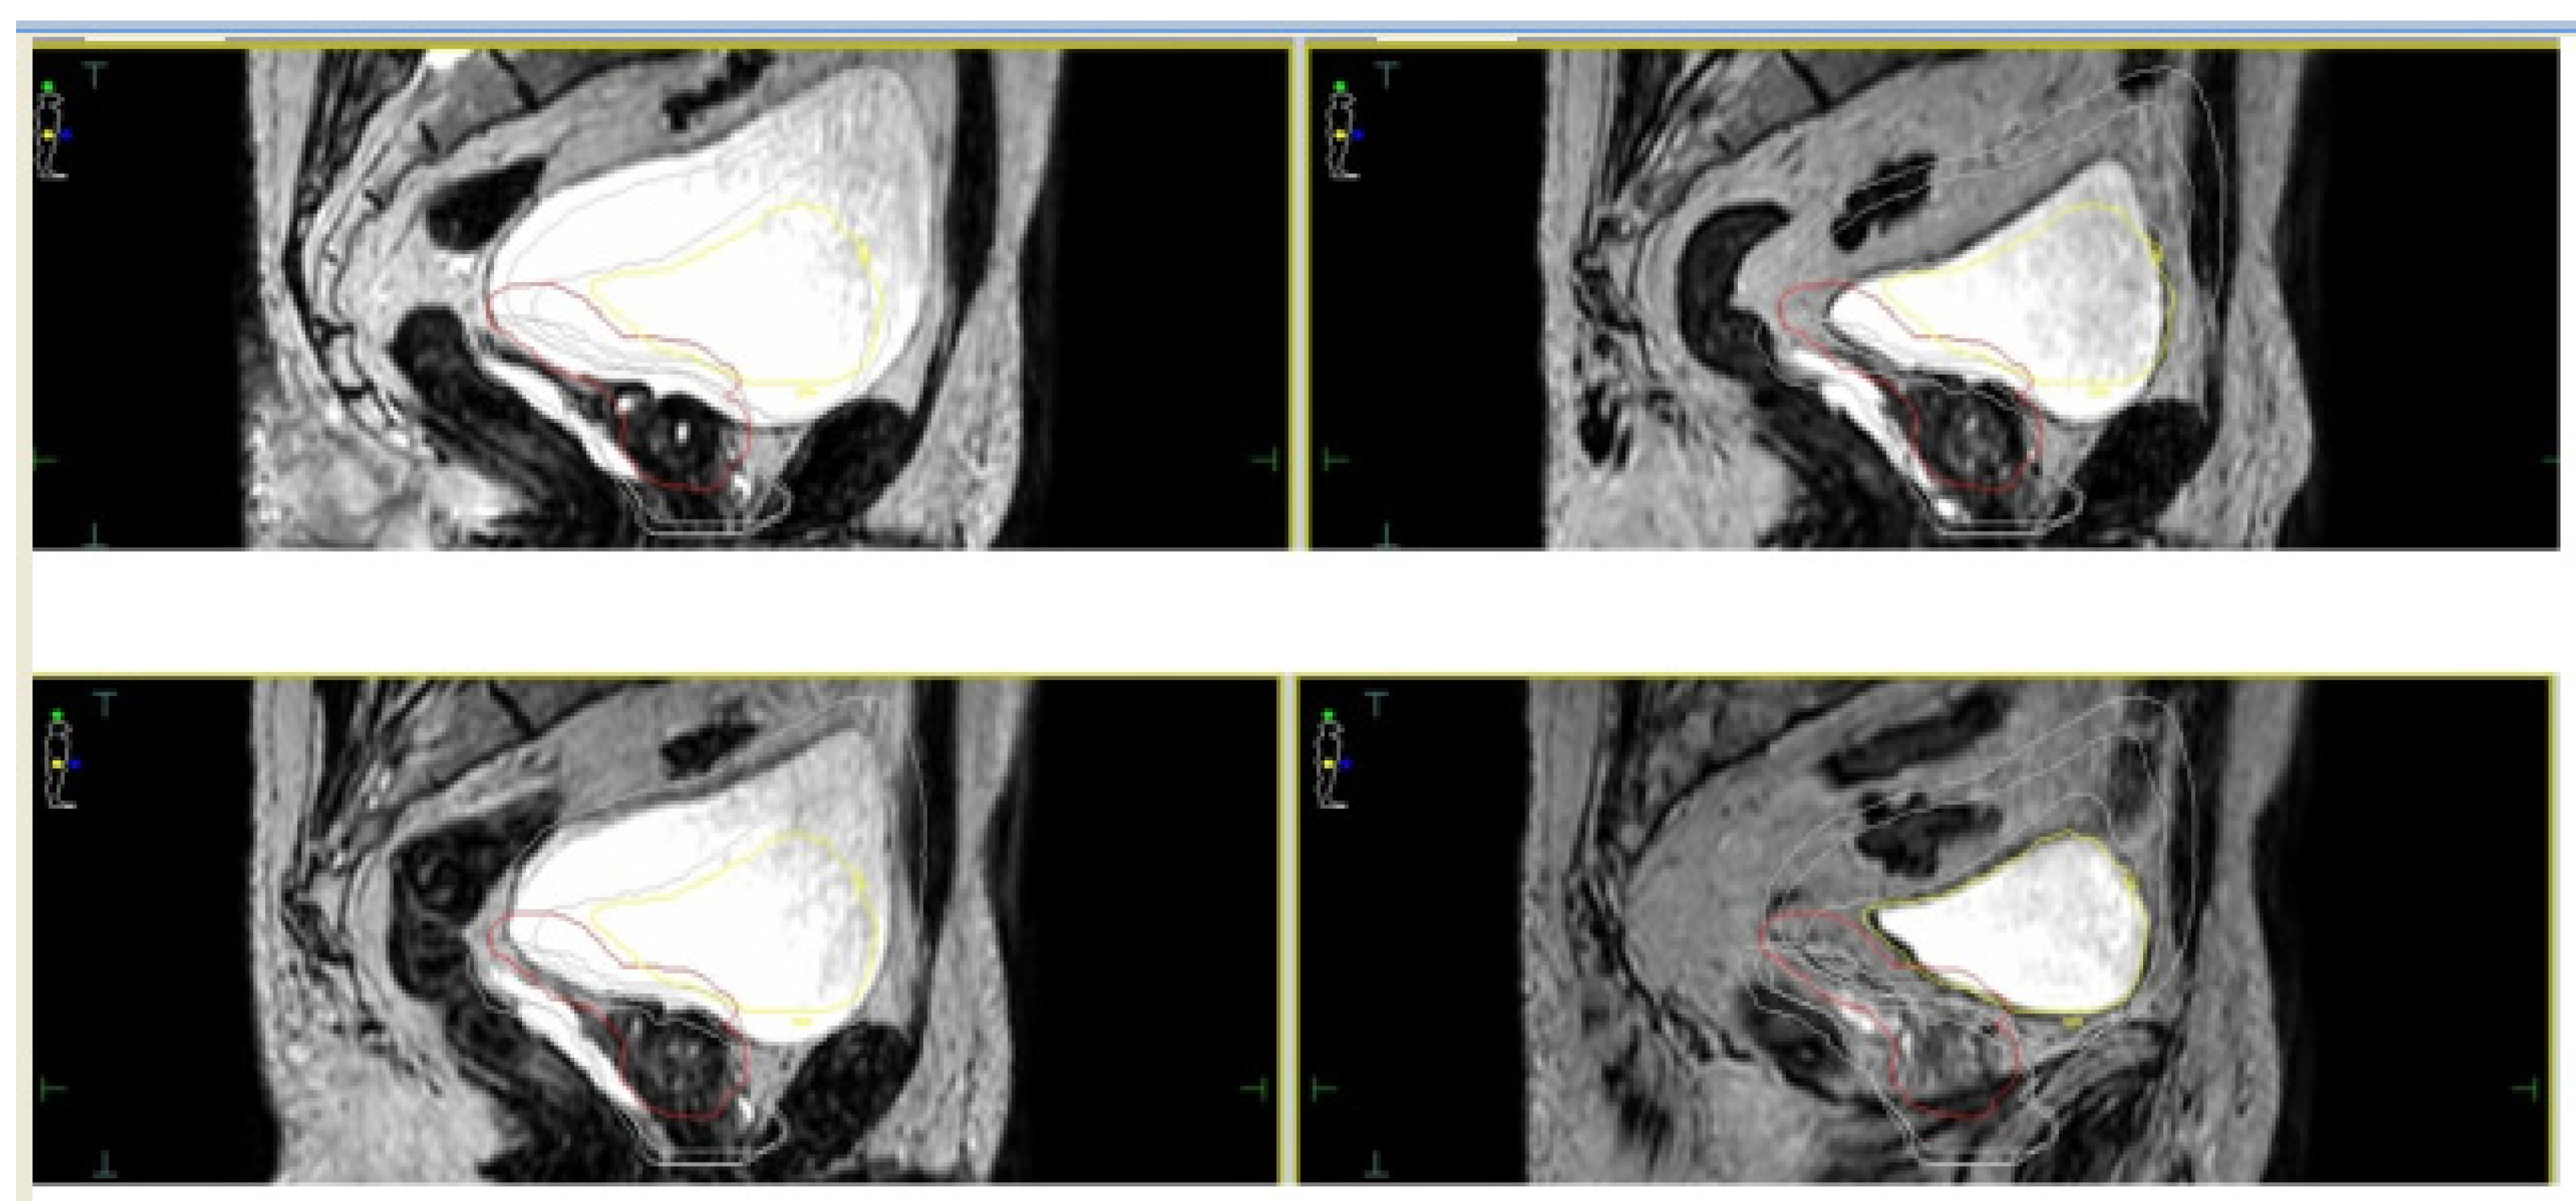

- Cuccia, F.; Mazzola, R.; Nicosia, L.; Figlia, V.; Giaj-Levra, N.; Ricchetti, F.; Rigo, M.; Vitale, C.; Mantoan, B.; De Simone, A.; et al. Impact of hydrogel peri-rectal spacer insertion on prostate gland intra-fraction motion during 1.5 T MR-guided stereotactic body radiotherapy. Radiat. Oncol. 2020, 15, 1–9. [Google Scholar] [CrossRef] [PubMed]

- Alongi, F.; Rigo, M.; Figlia, V.; Cuccia, F.; Giaj-Levra, N.; Nicosia, L.; Ricchetti, F.; Vitale, C.; Sicignano, G.; De Simone, A.; et al. Rectal spacer hydrogel in 1.5T MR-guided and daily adapted SBRT for prostate cancer: Dosimetric analysis and preliminary patient-reported outcomes. Br. J. Radiol. 2021, 94, 20200848. [Google Scholar] [CrossRef] [PubMed]

| Cuccia et al. [34] | 20 | Elekta Unity | 35 Gy/5 fractions | Assessment of the impact of rectal spacer on prostate motion | Significant impact on rotational antero-posterior shifts with consequently reduced prostate motion |